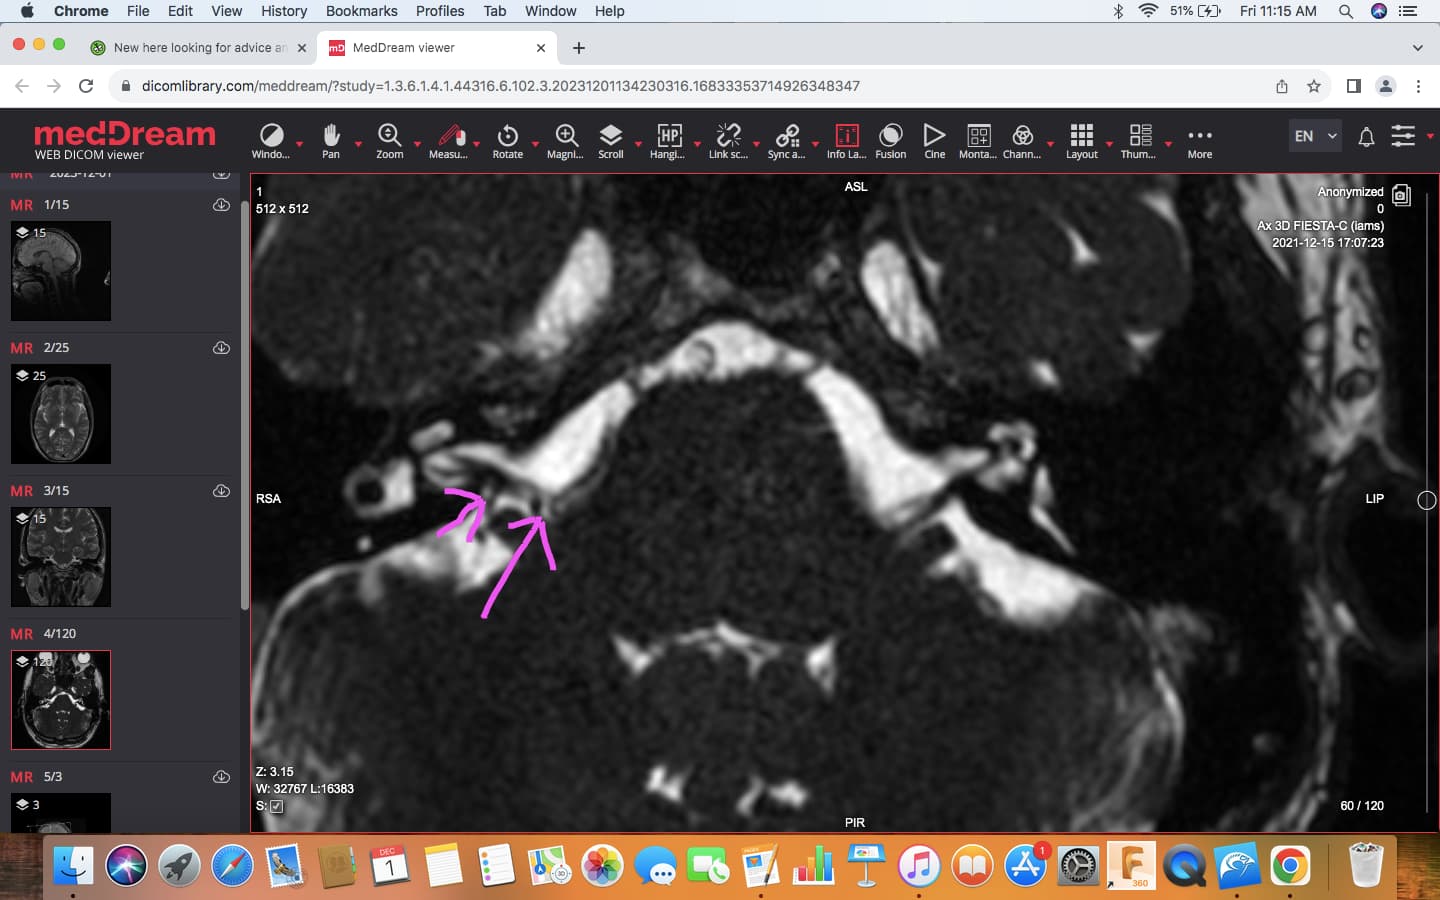

@sprinter, I think images like this may confirm some brainstem compression from the vertebral artery…

This MRI also shows an artery in contact with your vestibular nerve…

Just to help clarify what I think is going on here, I coloured in the vertebral artery, which pressing upon the brainstem…